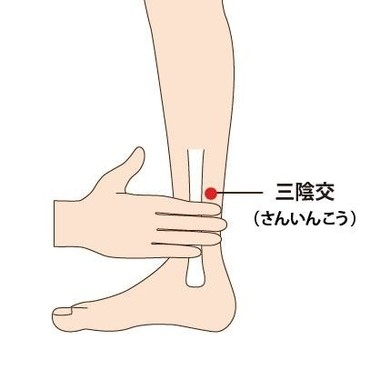

三陰交

足のすねの内側のくるぶしの1番高い部分から指4本分上に位置するツボです。

こちらは生理痛や更年期障害、足の冷え、血行不良などに効果が有ります。

更年期障害や生理痛に効果があると言われているように、特に女性に有効なツボと言われています。